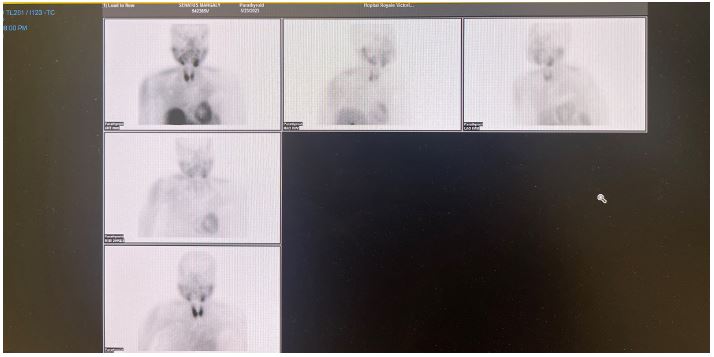

Images are Not Display Check it

Figure 2: Parathyroid MIBI scan showed no localization for parathyroid adenoma.